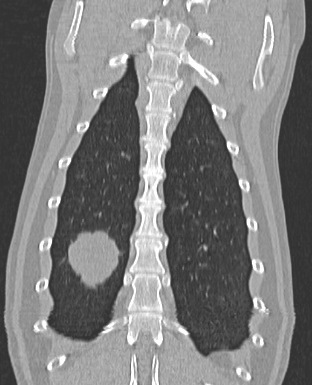

Fig 2a and 2b: Transverse and Coronal CT reconstructions of the same mass shown in figure 1.

Fig 3: Same case as figures 1-2: A second small (9mm) mass adjacent to a blood vessel is seen within a separate lung lobe. This nodule was not visible on screening radiographs. Other grey “spots” are branching blood vessels